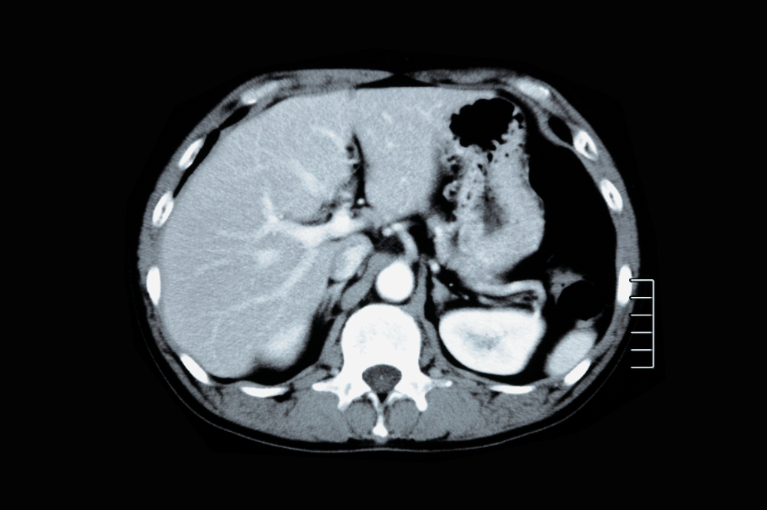

CT検査

内視鏡では診断が難しい病気に対して有効です。急性膵炎、胆嚢炎、虫垂炎などの診断に用いられ、体内の詳細な情報を得ることができます。